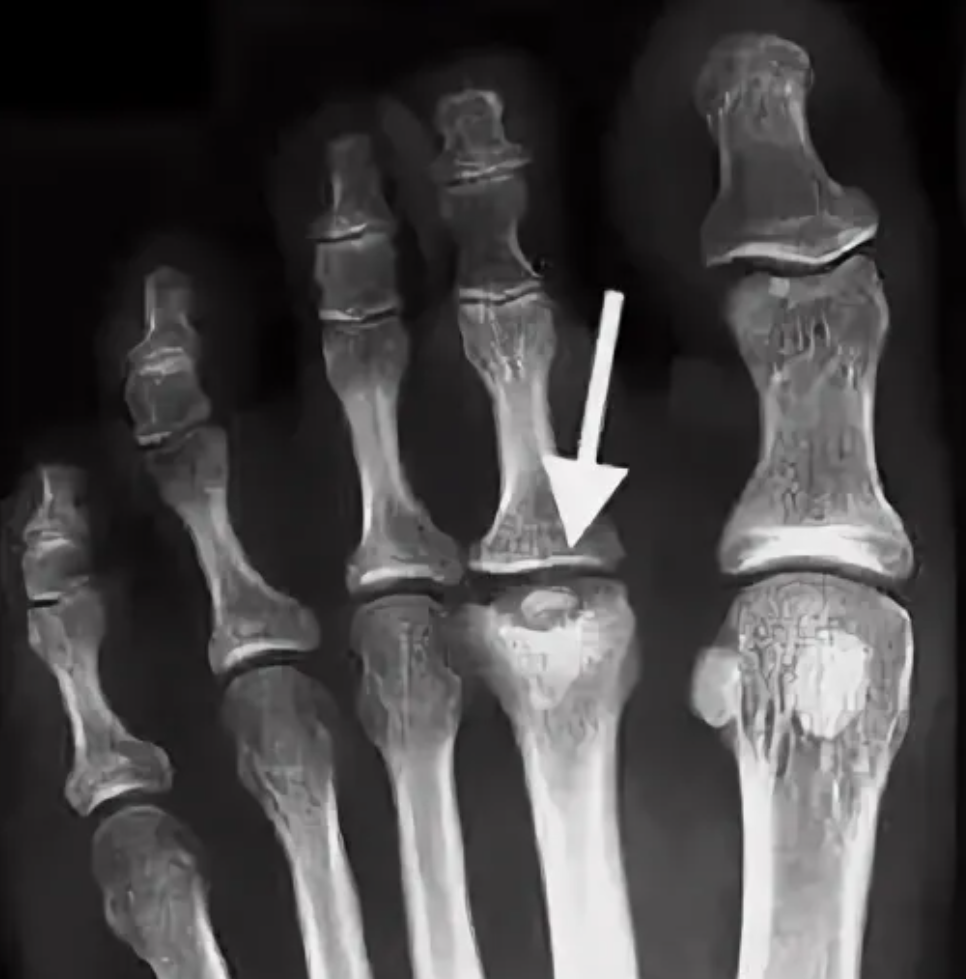

Конец бедренной кости, головки второй и третьей плюсневых костей, а также грудинный конец ключицы

Болезнь Келлера